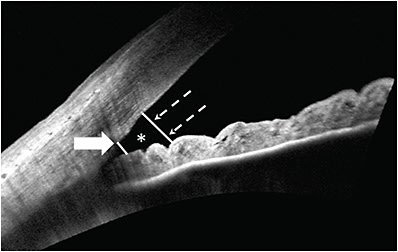

Potential clinical uses of AS-OCT include distinguishing open from closed angles, evaluating risk factors that may contribute to angle closure or predict progression to glaucoma, and assessing the effects of therapeutic interventions. Qualitative definitions and quantitative parameters have been established to allow evaluation of OCT for these purposes. A closed angle is one in which there is iridocorneal contact anterior to the SS (Figure 1).5,8 For quantitative assessment of the angle, an assumption is made that the trabecular meshwork is located approximately 500 µm to 750 µm anterior to the SS, and this is the basis for the parameters of the angle opening distance (AOD) 500 and 750, trabecular iris space area (TISA) 500 and 750, and angle recess area (Figure 2).4 Additional measurements of the anterior chamber (eg, anterior-chamber depth and width), lens (eg, lens vault [LV]), and iris (eg, iris thickness, iris curvature) have been defined as well.9 Multiple studies have evaluated the agreement of these parameters between different OCT devices. Angle measurements tend to be correlated but have poor agreement when time-domain and spectral-domain devices are compared with swept-source; therefore, they are not considered interchangeable.7,10-12